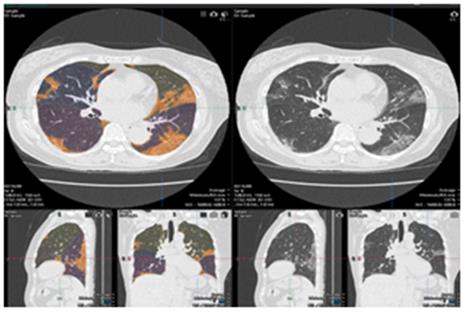

日本藤田医科大学携手佳能医疗共同开发新冠快速检测(CT)系统

日本藤田医科大学放射线学教授大野良司与佳能医疗系统株式会社合作开发了基于CT肺部图像的新冠肺炎解析软件。... -